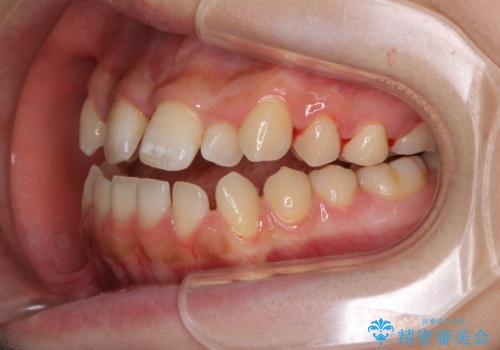

上顎骨を拡大したことで、下顎の歯列を上顎が受け入れられるようになりましたが、インビザラインでは咬み合わせを改善させることができなかったため、ワイヤー矯正にて仕上げることとしました。

ワイヤーを使用したものの、上下前歯のオープンバイトがなかなか改善されませんでしたが、患者希望により治療終了となりました。